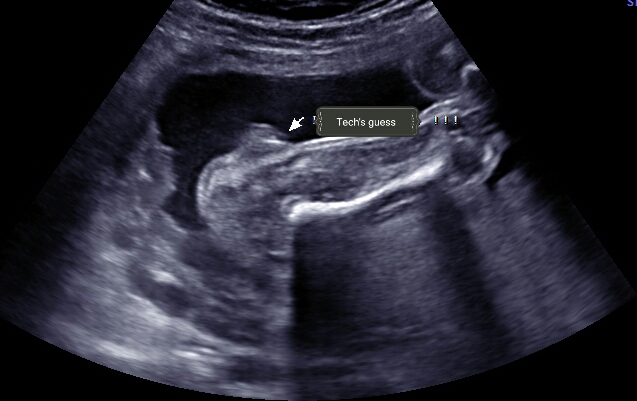

Attachment 39030

Same angle different picture

Wait, the tech actually guessed girl?! That second picture looks like a penis and testicles to me... that first one would have to be a PRETTY swollen vulva!

That was my thought! I don't have any more pictures. She only looked at it from this angle for two minutes, no between the legs or under bum angle.

Oh i forgot to answer.... I'm not sure why she didn't look between the legs. I tried asking more questions and she looked at this angle for maybe a minute or two and said it's definitely a girl. It's just weird that more than 90% of the people I've shown have said boy.